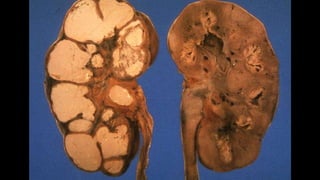

Renal Tuberculosis

 This can cause asymptomatic pyuria (white blood cells in the

urine) and can spread to the reproductive organs and affect

reproduction. In men, epididymitis (inflammation of the

epididymis) may occur.